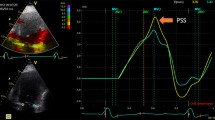

Echocardiographic studies were performed on commercially available ultrasound equipment (Acuson Sequoia, Siemens Medical, Mountain View, CA and Vivid-7, GE Healthcare, Milwaukee, WI) according to the standard method recommended by the American Society of Echocardiography. The LV volumes and ejection fraction (EF) were obtained by the modified biplane Simpson's method from the apical 4- and 2-chamber views. The LV wall was divided into 16 segments and the wall motion of each segment was visually evaluated and scored with the following scale: 1 = normal; 2 = hypokinesis; 3 = akinesis; 4 = dyskinesis; and 5 = aneurysmal. The average of the score of evaluated segments served as the WMSI. The mitral early diastolic flow (E) velocity and late diastolic flow (A) velocity were measured and the E/A ratio calculated. The deceleration time of the mitral E wave was also measured and Doppler tissue imaging was obtained from the apical four-chamber view. The digital images were obtained at optimal frame rates (≥ 30 frames per second). Images were stored in digital cineloop format (Prosolv Cardiovascular solutions, Indianapolis, IN) for offline analysis by vendor customized 2-D Cardiac Performance Analysis software (2D CPA, TomTec multimodality imaging solution, Munich, Germany). 2D CPA is a speckle tracking based analysis tool that can analyze 2D data from various ultrasound machines and is an extension of velocity vector imaging software that has been previously validated with sonomicrometry [8, 9] and magnetic resonance imaging [10, 11]. 2D CPA, similar to velocity vector imaging, determines myocardial motion from a user-defined tracing along the endocardial border. Both users defined endocardial and automated subepicardial borders are traced throughout one cardiac cycle by successive application of a series of tracking steps. From this motion, the myocardial velocity, longitudinal and radial strain are calculated for both endocardial and subepicardial regions along the trace. Longitudinal systolic strain from endocardial and subepicardial regions respectively was obtained from 6 segments and from lateral and septal wall segments in apical 4-chamber views. Circumferential strain and radial strain were obtained from 6 segments in short-axis views of the LV at the level of papillary muscle. Assessment of the LV strain was regarded as suboptimal when either: 1) speckle tracking could not be obtained for at least 4 of the 6 myocardial segments in apical 4-chamber or short-axis views; or 2) a theoretically unacceptable value or values were obtained. Offline analyses were independently performed by one observer who was not involved in image acquisition nor had knowledge of other echocardiographic measures of LV function. Echocardiographic indices were measured as per the recommendations of American Society of Echocardiography [12]. Serial changes in global strains and WMSI were compared for predicting an improvement of LV ejection fraction (EF > 5%) on follow-up.

Among all the clinical variables that were entered into a univariate logistic regression analysis only two were significantly associated with outcome improvement in LVEF at follow up. The change in endocardial longitudinal strain (OR 1.2, 95% CI 1.03 to 1.42, P = 0.01) and the change in epicardial longitudinal strain (OR 1.2, 95% 1.03 to 1.46, P = 0.02) were significantly associated with the improvement in LVEF, independent of the location of STEMI and the presence of underlying multivessel disease (Figures 1, 2) (Table 5).

Panel A and B show attenuated global longitudinal endocardial strain in two patients with anterior wall myocardial infarction. Note the minimal improvement in longitudinal strain in the first patient (panel C) which has accompanied no improvement in LVEF. In contrast, panel D shows marked improvement in longitudinal strain on follow up in the second patient which is accompanied by significant improvement in LVEF.